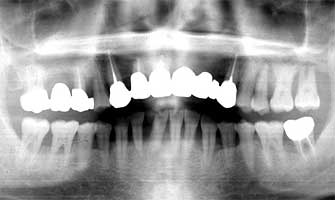

Dentistry medical treatment

Fig. 18 Mr H 20 years after the first medical examination. 46 years old.

All of his lower teeth have also reached the last stage of gingivitis. His upper teeth also look like they are on the way out

Mr H He was 26 years old at the first medical examination. Male (Fig. 15-16-17-18)

At the time of first medical examination except for one big cavity his teeth appeared to the eye to be healthy. However at that time quite a lot of tartar was removed from his teeth. After the first treatment was complete he stopped visiting, even though it was pointed out the necessity of maintenance from time to time. Later he complained about new abnormalities. From this point he started visiting every three years. Although regular maintenance of scaling was recommended each time, 20 years passed without this happening. By not having regular maintenance his teeth degenerated which sadly should have lead him to understand the meaning and importance of maintenance. However to learn this lesson he has had to sacrifice a lot.

Mr H’s 20 years with maintenance can not be precisely predicted but what is certain is that without it his life was greatly affected. As verification I want to discuss the example of Mr K. Mr K, who was 44 years old at the time of first medical examination was in the same advanced stage of gingivitis as Mr H was at 41 years of age. The upper molar had developed to an early advanced stage of gingivitis. Generally since extra burden is placed on the upper front teeth when the upper molars are taken, it is thought that the upper teeth are more vulnerable than lower teeth.